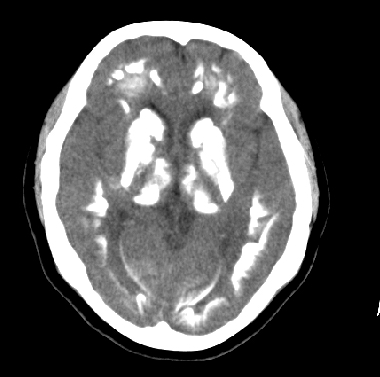

女性 38岁 病人脚弓反张 8岁以后不能行走 今年查pth11.9ng/ml(正常28ng/ml)

谢分享----甲状旁腺功能减退

这么弥漫的钙化还第一次见。

考虑甲状旁腺功能减退症,该病是因甲状旁腺激素分泌减少或功能障碍所引起的少见病。其特点是低血钙,高血磷,且血pth极低。因低钙常可引起神经精神激惹症状,包括手指,趾,口角麻木,严重时可出现肌肉痉挛,喉哮鸣和惊厥,甚至癫痫样发作,有的可出现抑郁症及精神失常。长期的高磷血症可引起脑内结构对称性多发性钙化,特别是小脑和基底节的钙化可致锥体外系症状,而钙化的ct表现为类似于脑出血的密度增高影。

原发性甲状旁腺功能减退症和fahr病都有神志上的改变等症状,且头颅ct检查均可见颅内出现钙化。但fahr病无pth低下,ct表现钙化影在大脑半卵圆中心皮髓质交界处、丘脑、小脑齿状核等处。 而甲状旁腺功能减退症pth极低,ct虽可见钙化影,但部位在小脑和基底节等处。